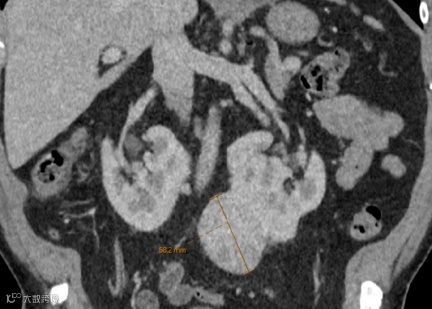

男,55岁,马蹄肾合并双肾多发结石,右肾积水(泌尿系气泡为导尿术后改变)。